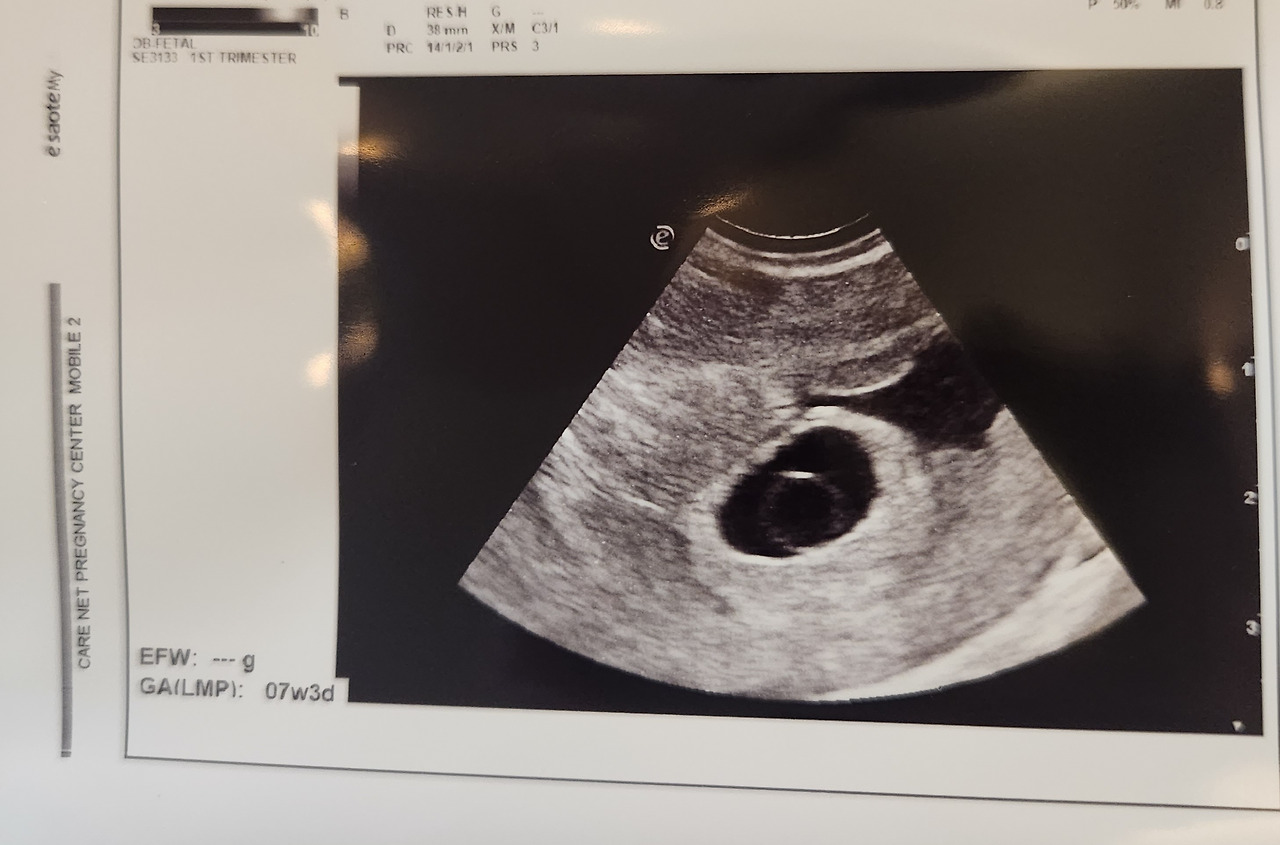

겨우 아기가 숨어 있던 아기집을 찾을 수 있었다.

20230227_142854.jpg 다행이라고 생각했다, 존재해 줘서

총 1시간, 저 작은 배를 훑어서 겨우 너의 존재를 찾았는데